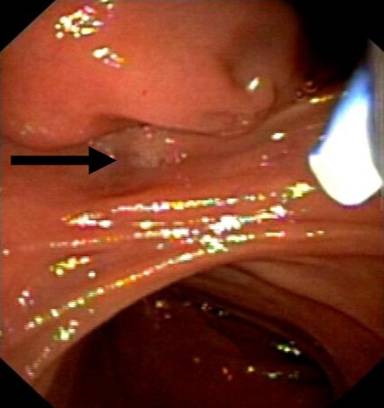

Computed tomography recognized a mass of the duodenum (Figure 1). However, magnetic resonance imaging did not reveal any lesion. Radiological differential diagnosis included gastrointestinal stromal tumor or adenoma. A magnetic resonance cholangiopancreatography was performed showing dilatation of the common bile duct (diameter equal to 9 mm) and gradually narrowing of its diameter downwards. Endoscopic retrograde cholangiopancreatography (ERCP) revealed a submucosal tumor located in the second portion of the duodenum. The lesion was seen as a large pedunculated polypoid mass originating from the second part of the duodenum in close proximity with the ampulla of Vater (Figures 2 and 3). No cholangiography was performed due to failure of cannulation of the bile duct. The pancreatic duct was normal without dilatation in its body or narrowing of its size. A sphincterotomy was performed 6 mm along the pancreatic sphincter, as it is considered an endoscopic therapy for chronic pancreatitis with papillary stenosis [8]. Two months after the procedure of sphincterotomy, the patient had another episode of acute pancreatitis without jaundice. Hence, the obstruction of the pancreatic duct due to the intermittent movements of the mass was considered as the cause of the episodes of acute pancreatitis. The patient was referred for surgical consultation and regional resection was decided. The operation was performed one month after the last episode of acute pancreatitis. Intraoperatively (Figure 4), there was no sign of lymph node metastases or local extension of the tumor.

Figure 3. Distal view of the tumor. The opening of the papilla (arrow) lies outside of the submucosal tumor. |